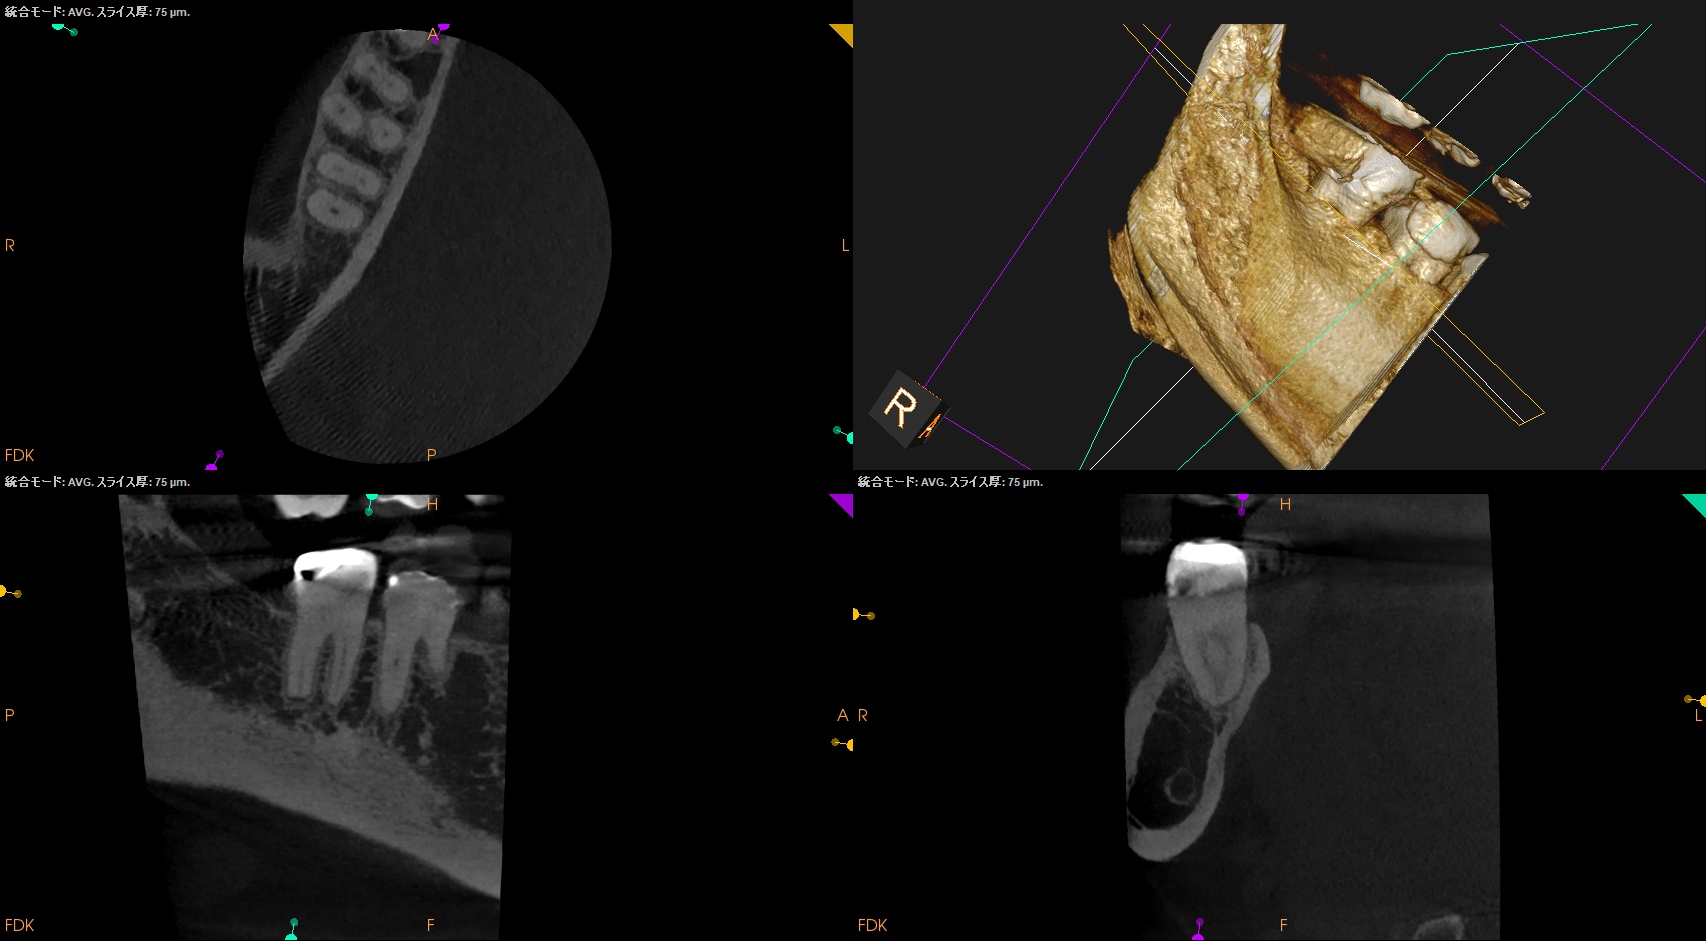

術後にPA, CBCTを撮影した。

MB

ML

D

問題はないだろう。